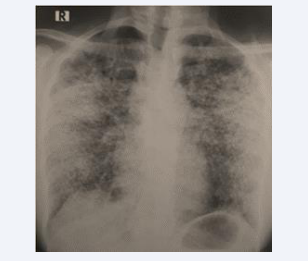

However, at the end of the six-month anti-tuberculous treatment, the patient experienced clinical worsening with dyspnea progressing to Mmrc stage III, profound anxiety, and radiological deterioration. A follow-up chest X-ray revealed the presence of diffuse bilateral micronodules (Figure 2).

Figure 2 Chest X-ray after 6 months of anti-tuberculous treatment showing diffuse bilateral micronodule.

Figure 2: Chest X-ray after 6 months of anti-tuberculous treatment showing diffuse bilateral micronodule.